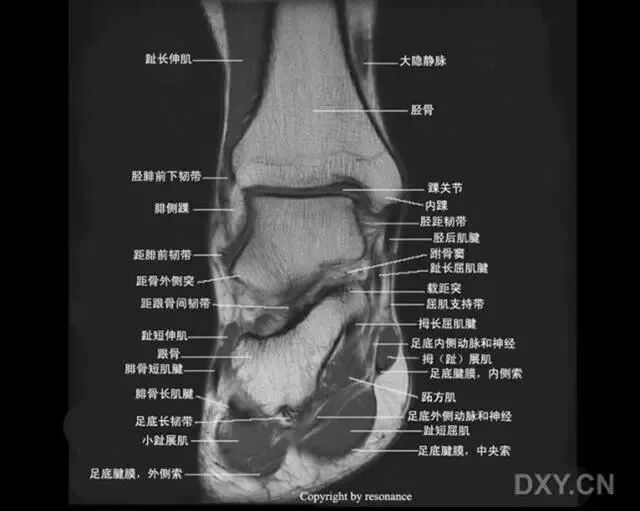

距骨在踝穴内有无倾斜,会通过影响关节面接触面积而影响关节所受应力的大小。有轻度倾斜,关节面所受到的应力会因为承重面积变小而明显增加。

旋后位扭伤最为常见;

距骨体前宽后窄,当踝关节背屈时,其宽部进入踝穴,能防止踝关节向后脱位;当跖屈时,其窄部进入踝穴,则关节不稳,易向侧方活动。